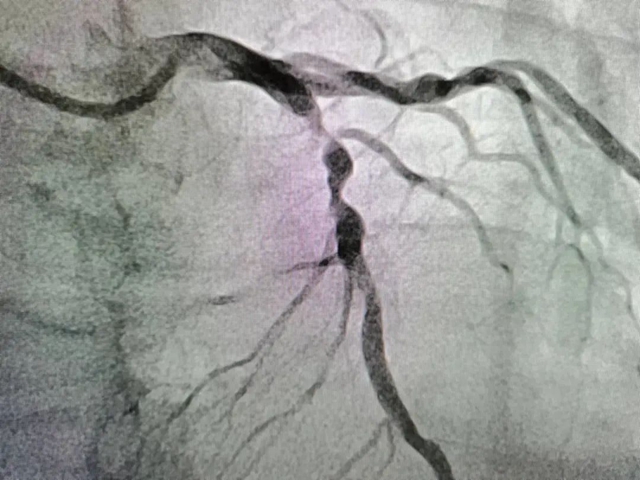

经医生接诊后为匡阿姨完善了相关检查,终于找到了病因:匡阿姨冠状动脉病变严重,存在心肌梗死,冠状动脉造影提示右冠脉内大量血栓,前降支重度狭窄。

前降支术前造影